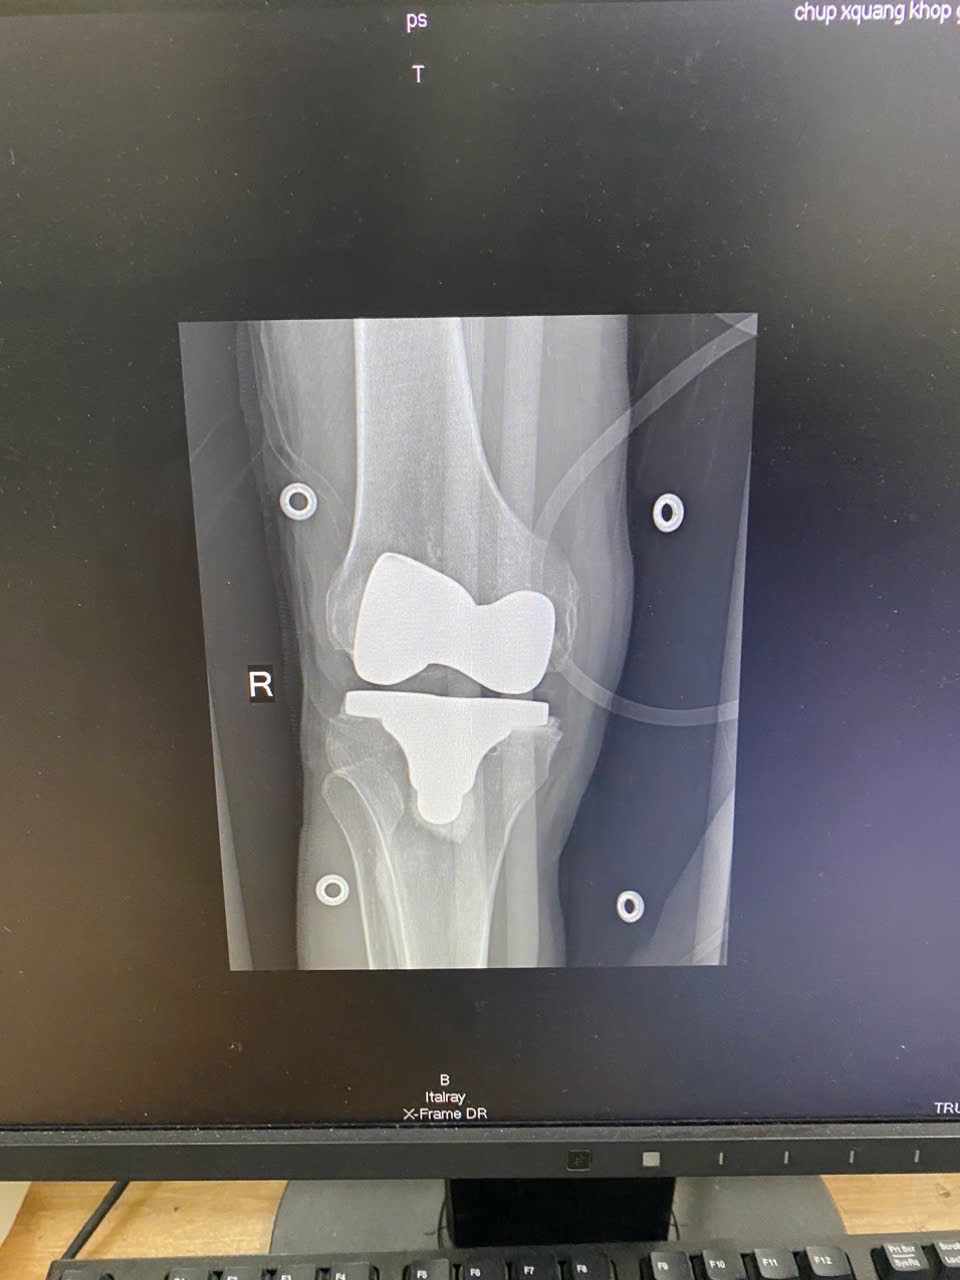

⚕️ Trước tình trạng tổn thương phức tạp và nặng, bệnh nhân được chỉ định phẫu thuật thay khớp gối theo hình thức chuyên gia.

👨‍⚕️ Ca phẫu thuật được thực hiện bởi ê-kíp chuyên gia từ Bệnh viện Việt Đức phối hợp cùng BSCKII Nguyễn Trung Kiên - Trưởng khoa Ngoại, TTYT KV Đoan Hùng

📈 Kết quả: Ca mổ diễn ra an toàn, thuận lợi. Sau phẫu thuật, bệnh nhân có cơ hội cải thiện đáng kể tình trạng đau, phục hồi chức năng vận động và nâng cao chất lượng cuộc sống.